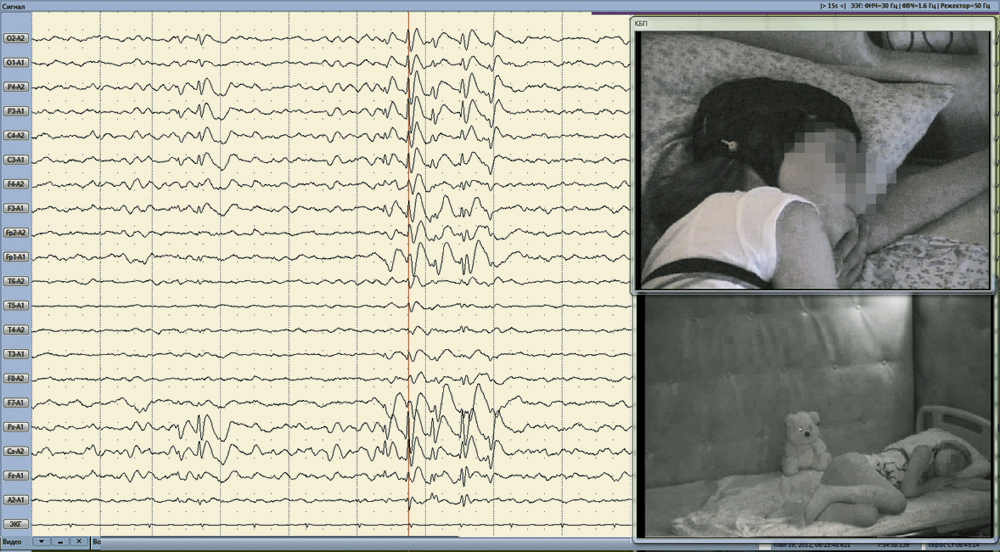

Электроэнцефалографы-регистраторы «Энцефалан-ЭЭГР-19/26» с комлектами видеооборудования и c ПМО «Энцефалан-Видео» – наилучшие инструменты длительного ЭЭГ-видеомониторинга в различных условиях проведения исследования для тонкого анализа различных проявлений эпилепсии

Полностью синхронизированная длительная многоканальная регистрация электроэнцефалограммы и видеоинформации о состоянии пациента является «золотым стандартом» при дифференциальной диагностике эпилепсии.

Синхронный просмотр ЭЭГ и видеозаписи при мониторинге или при последующем анализе может проводиться на одном или двух мониторах.

Возможен просмотр видеозаписи с нормальной, ускоренной, или замедленной скоростью, а также режим стоп-кадра и быстрый переход к любому моменту данных ЭЭГ-видеомониторинга (по указанному времени, маркерам или меткам).

Точность синхронизации ЭЭГ- сигналов с видеоданными при записи и воспроизведении – 1 кадр.

Обеспечивается быстрый переход к видеокадру, соответствующему выбранному моменту времени на записи ЭЭГ, и к фрагменту ЭЭГ, соответствующему выбранному видеокадру.